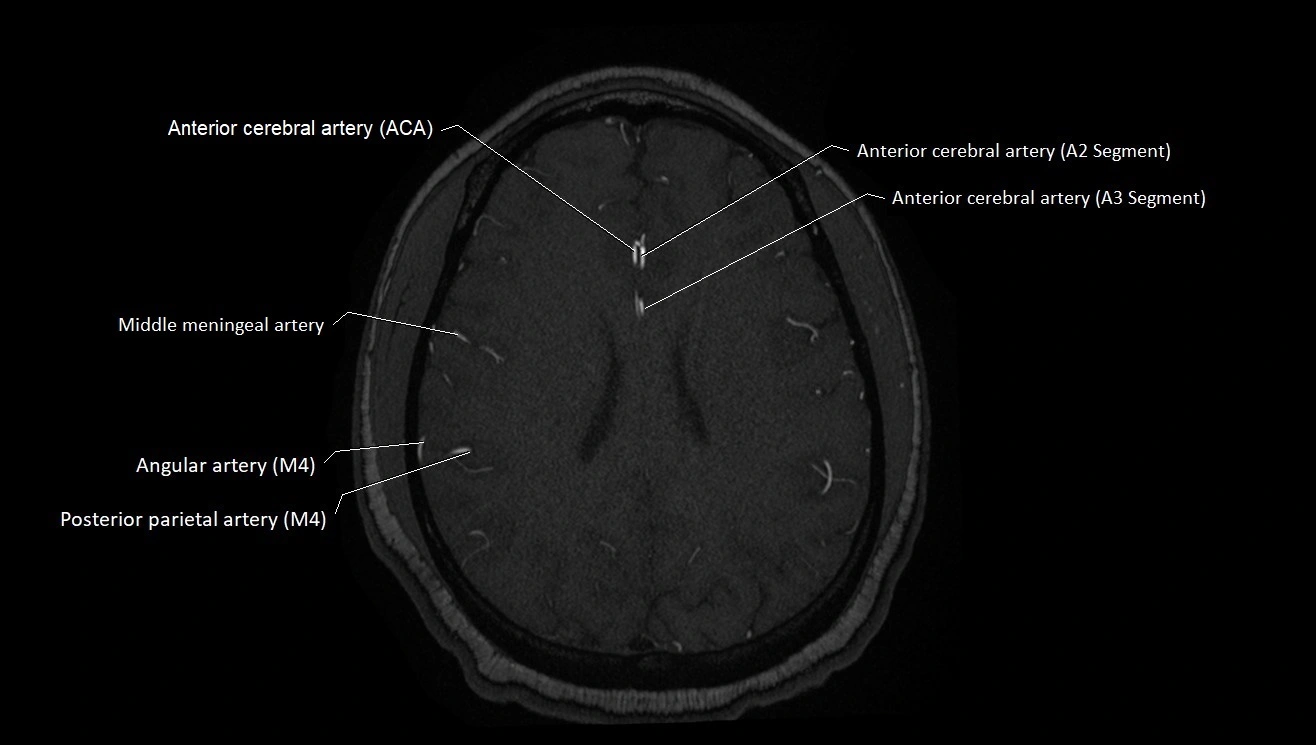

CT images

image